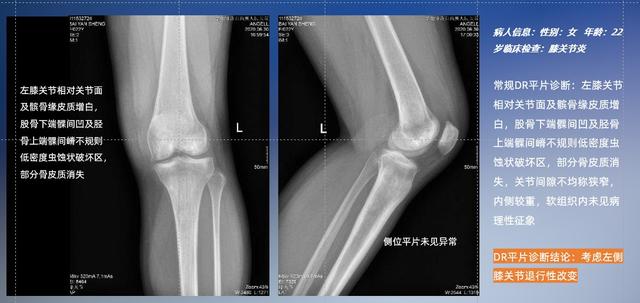

以膝關節疾病檢查為例,膝關節在解剖學意義上是一種較為復雜的最大關節,由脛骨上端、股骨下端及髕骨組成。在股骨與脛骨的關節面之間存在兩塊半月板,分別處于內側、外側。膝關節的運動主要為伸、屈,在半屈位時可進行小幅度的旋外、旋內運動。隨著現代人們體育生活以及肥胖的增加,膝關節疾病出現高發趨勢,特別是關節磨損、膝關節炎與骨關節炎等關節退行性改變,長時間的內翻負荷會造成內側關節軟骨、骨性關節面的磨損。目前針對此類疾病的檢查主要為平片下的負重位檢查、CT檢查以及MRI檢查,相較于非負重位檢查,負重位檢查能更加真實反映膝關節結構中脛骨、股骨、髕骨實際對位關系和關節面的形態特征及關節間隙大小,對膝關節骨關節病診斷準確率高。

普通平片掃描與WR-3D掃描前后診斷結果對比

在負重位狀態下,數字化X線三維掃描與重建,能夠更好的呈現受檢者關節受力改變的狀態。安健科技創新的WR-3D動態三維影像重建系統,通過數字化X線攝影完成三維掃描并重建三維影像信息,包括斷層圖像重建、MPR多平面重建、MIP重建以及VR體繪制。其掃描時間短,劑量相較于CT設備大幅縮減,同時成本更低,在臨床診斷以及醫療方案制定中具有極大的價值意義。而相較于普通平片下的負重位掃描,負重位動態三維影像重建技術能夠避免二維狀態下的組織結構重疊、密度分辨率不足、組織解剖結構難以分辨等問題。WR-3D支持多角度的三維觀察,能全面的呈現被檢查部位在多個角度下的三維影像信息,極大的降低了二維負重位檢查帶來的漏診率。